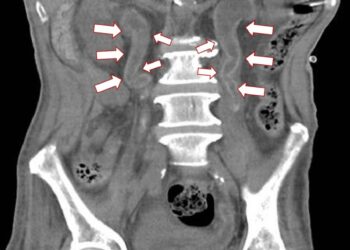

標籤: 記者蕭麗鳳/彰化報導 https//youtube/Z5IyLdyQSYY 61歲梁姓男子半年內因為泌尿道感染住院多達6次,日前再度發燒及泌尿道感染,轉院到衛福部彰化醫院就醫,多科會診發現,包括腎臟及輸尿管等泌尿道系統被一層像是水泥、蛋殼的鈣化物覆蓋,被稱為Encrusted